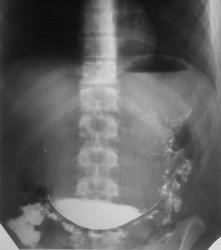

Дежурство. Вторая половина дня. Под конвоем привозят молодого человека из зоны. Боли в животе.Четвертый день после начала рентгенисследования ЖКТ.

Коменты на 3-й день ...."Гастроптоз. Дуоденостаз".

Разницы между снимком на третий день и тем, кторый сделал мой лаборант на 4-й день, практически нет...

Думаю, что о птозе органа, о котором упомянули в направлении, говорить некорректно, о наличии птоза можно утверждать, когда орган  опущен полностью. А здесь верхняя часть желудка на месте, опущен лишь нижний отдел - антрум - удлиненный желудок, декомпенсированный стеноз выхода... 12 п.к. - не виновата вообще.

И еще...цитата из записи в амбулаторной карте - "Эвакуация только при насильственной компрессии"...хотя далее - "луковица 12 п кишки не изменена".....

1. День - скопия (в зоне) - гастроптоз, дуоденостаз

2. Досмотр на 2- й день - то же самое

3. Досмотр на 3-й день - то же самое

4. На четвертый день - привозят в ургентную клинику к вечеру, делаем снимок - заключение декомпенсированый стеноз выходного отдела желудка.

Наталья Васильевна, конечно- отмыли; конечно - сделали ФГДС (стеноз подтвердился, пройти в луковицу не удалось); конечно - прооперировали (нашли кисту головки поджелудочной железы, гематому в этой кисте...все это вскрылось в 12 п кишку); естественно - был и перигастрит (очевидно он причина рубцового сужения); наложили передний гастроэнтероанастомоз....подправится маленько, там уж будут дальше думать, что с ним делать (разгребать в наших условиях ТОТ конгломерат, который нашли, это потерять молодого человека....).